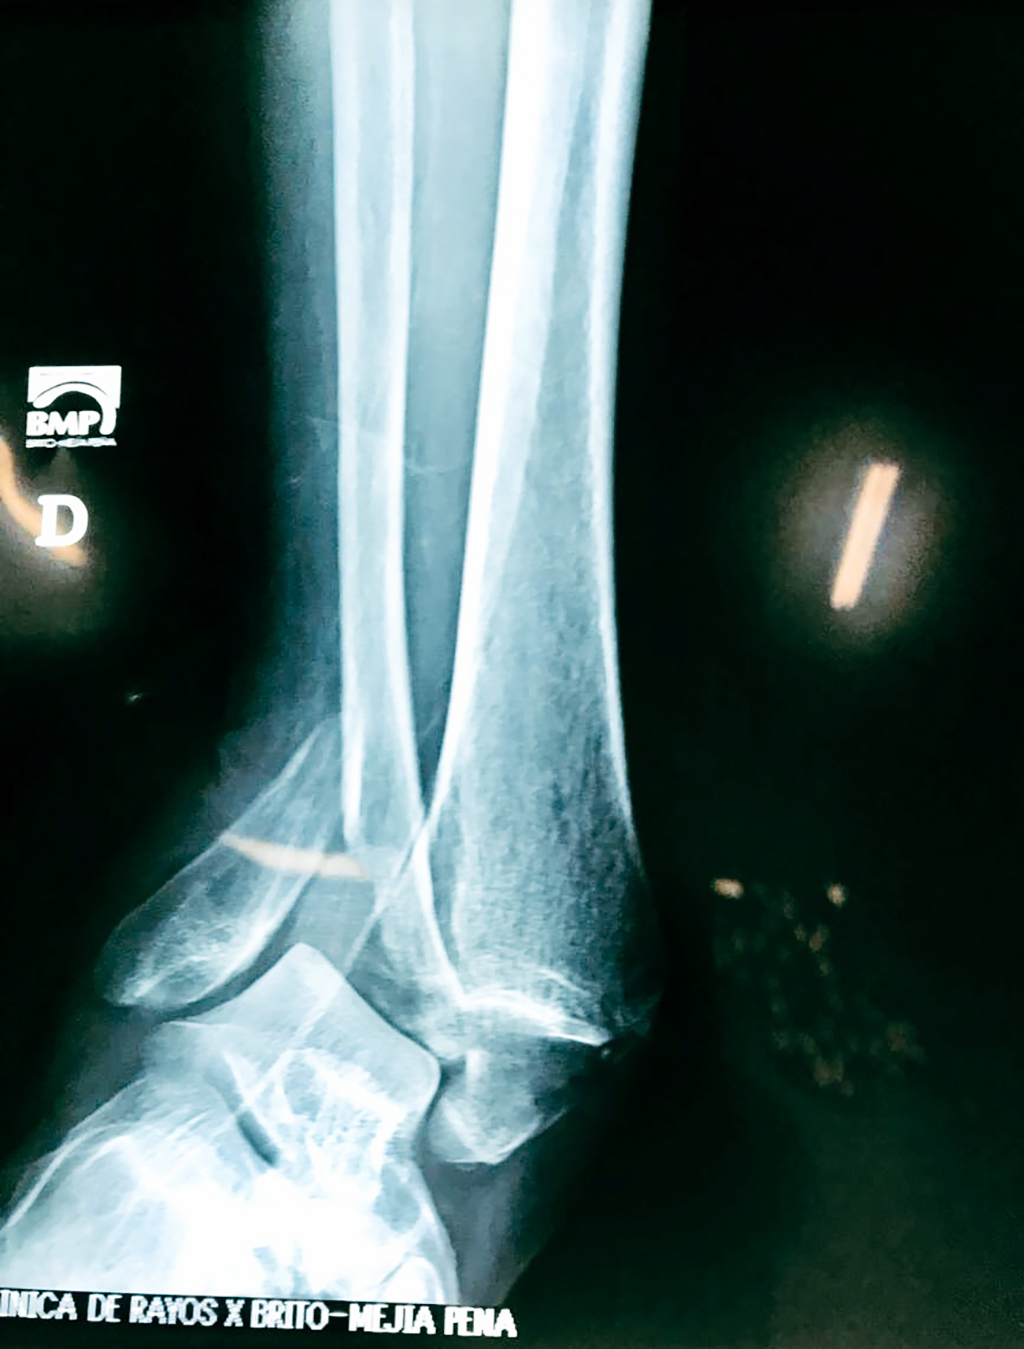

Una fractura de tobillo es la rotura de uno o más de los huesos del tobillo. Estas fracturas pueden ser:

Algunas fracturas de tobillo pueden requerir cirugía si:

- Los extremos de los huesos están desalineados entre sí (desplazados).

- Los tendones o ligamentos (tejidos que sujetan los músculos y los huesos entre sí) están rotos.